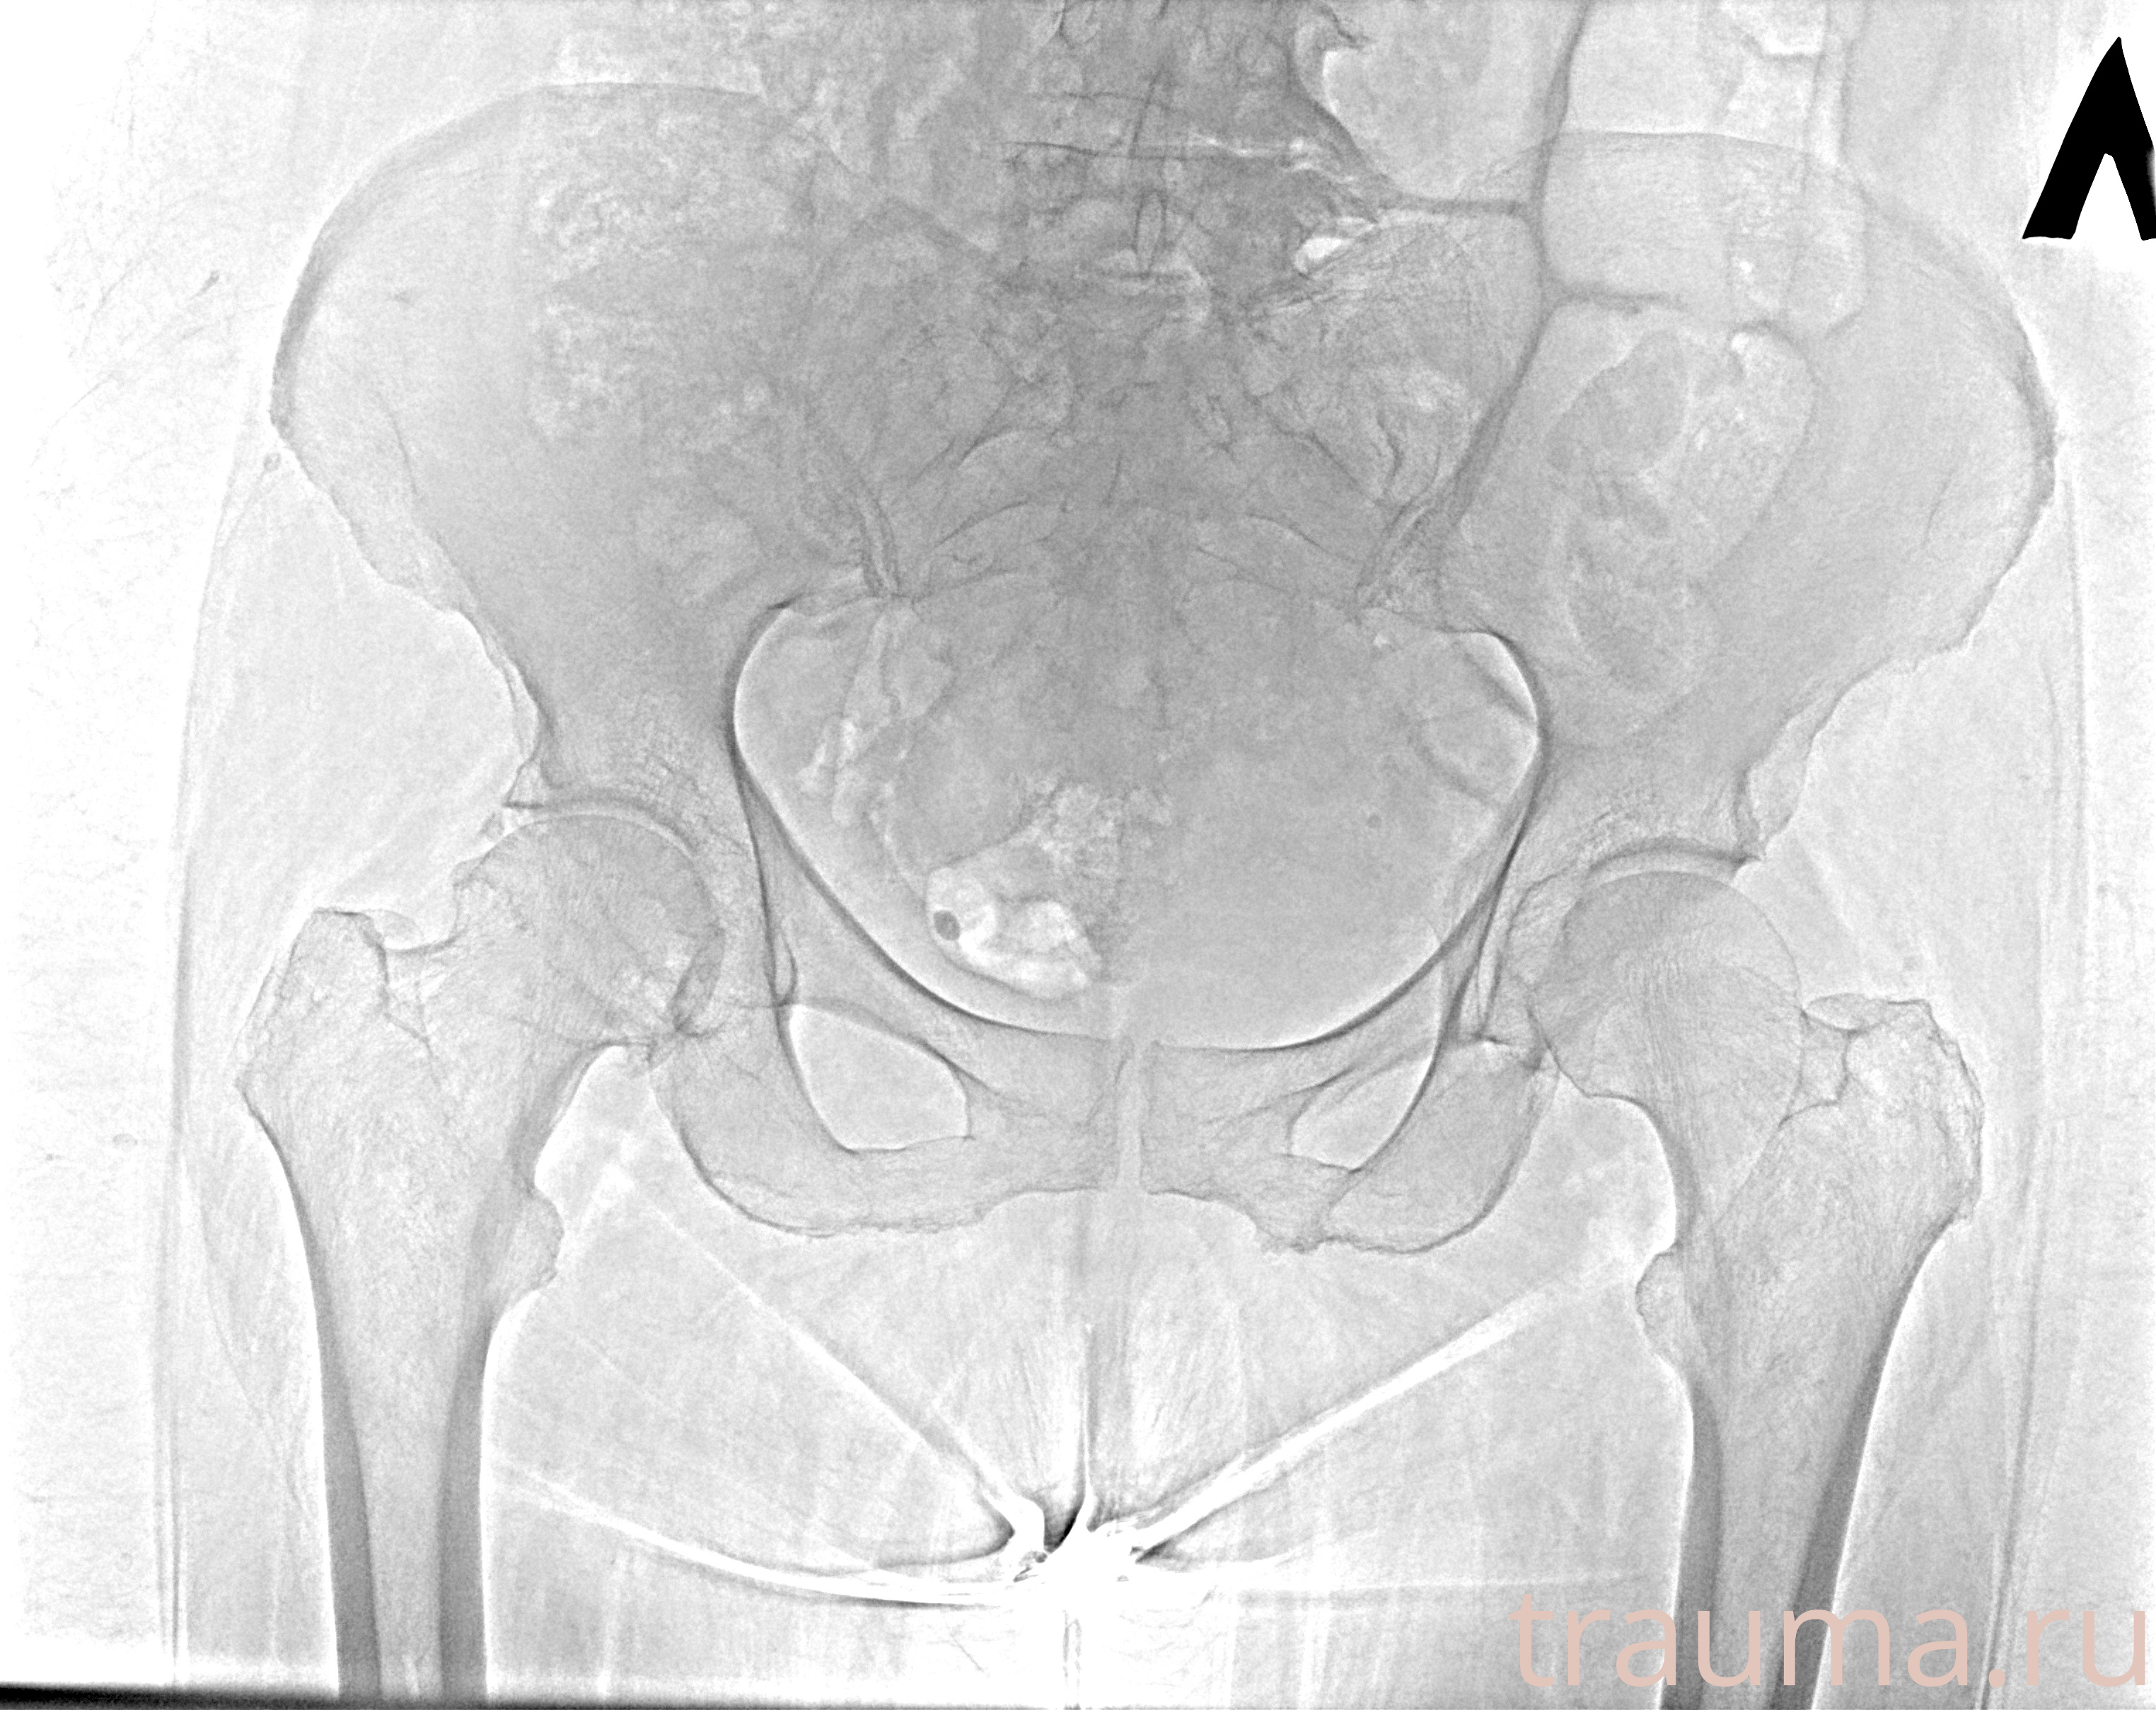

Рентгенограммы

Рентген на дому: по вашему адресу приезжает врач-рентгенолог, травматолог-ортопед с мобильным рентгеновским аппаратом, проводит диагностику травмы или заболевания, делает необходимые рентгенограммы, дает рекомендации по дальнейшему лечению. Получить качественные снимки в домашних условиях возможно благодаря уникальной методике, разработанной МосРентген Центром для института  Склифосовского